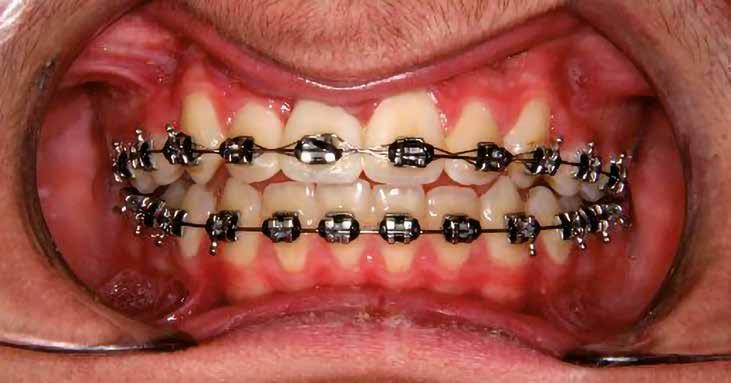

A kezelés első lépéseként az összes maradó fogra breketteket rögzítettünk. A felső fogív nivellálása, a ferde tengelyállá-

sok korrigálása, valamint az impaktálódott fog előtöréséhez szükséges hely megteremtését követően, egy merev acél ív segítségével stabilizáltuk a fogakat. Ezt követően elvégeztük a jobb felső nagymetszőfog sebészi feltárását. A fog koronáját csupán lágyrész borította, ezért nem volt szükség a csontállomány elvételére. A felszabadítás során egy 975

nm-es hullámhosszon pulzáló üzemmódban alkalmazott lézert használtunk (LaserHF standard, Hager & Werken). A teljesítménye 3 W, az aktív ciklus-idő 50%-os, a vezetőszál átmérője pedig 0,4 mm volt (2. ábra). A lézert 150 másodpercen keresztül alkalmaztuk. A fogat borító lágyrészek eltávolítását követően egy láncos brekettet rögzítettünk a metszőfog bukkális felszínére. A műtétet követően nem tapasztaltunk vérzést, nem alakult ki oedema, valamint a páciens sem számolt be fájdalom vagy bármely egyéb kellemetlenség fennállásáról. A felszabadítást követően a páciens minden hónapban háromszor jelent meg a felszabadított területre ránövő lágyrészek és az íny lézeres eltávolítása céljából. A beavatkozások során ugyanazt a lézer készüléket használtuk, mint amivel a felszabadítást végeztük. Közvetlenül a felszabadítást követően megkezdtük a fog finom extrudálását a láncos breketthez kötött füzérgumi segítségével.

6 hónapon keresztül tartott. Ennek megfelelően a fog körül található szövetek a felszabadítás, valamint a havi kontrollok során 975 nm-es (több mint 25 J/cm2 energiasűrűség) és 660 nm-es hullámhosszúságú (12–18 J/cm2 energiasűrűség) lézersugarakkal is megvilágításra kerültek. Az impaktálódott fogat megközelítőleg 7 hónap alatt tudtuk megfelelő pozícióba mozgatni (3. ábra). Az orthodoncia kezelés aktív szakasza 18 hónapon keresztül tartott. A fogívek végső nivellálását és a fogak végleges pozícióba rendezését 0.018 × 0.025-ös acélívekkel végeztük.